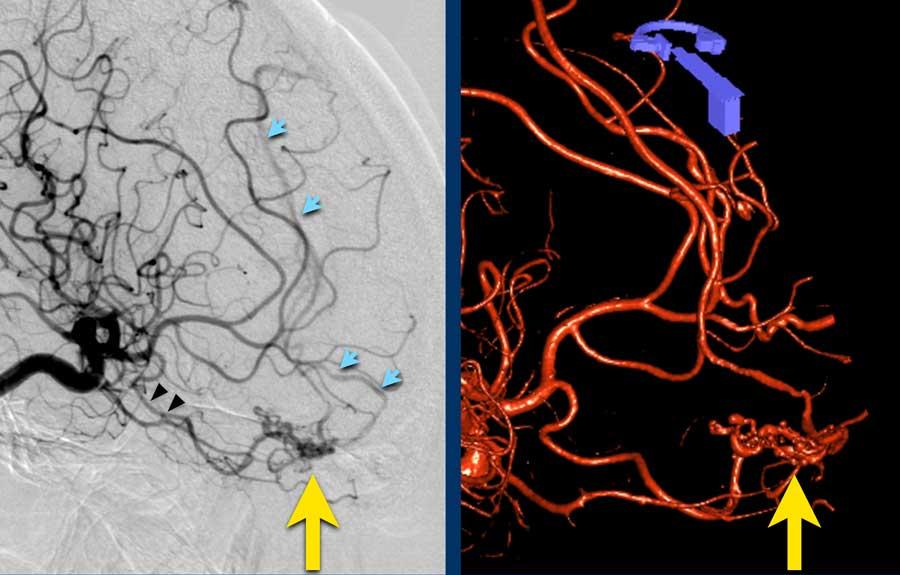

Các hình ảnh thuộc về một bệnh nhân nữ trẻ tuổi với triệu chứng đau đầu khởi phát đột ngột vài giờ sau khi sử dụng cocaine.

Bệnh nhân nhập viện với tình trạng liệt nửa người bên trái.

- A – NCCT cho thấy xuất huyết thùy não ở thùy đỉnh phải với lan rộng vào hệ thống não thất (chấm nhỏ tại lỗ Monroe).

- B – quan sát thấy các tĩnh mạch dẫn lưu lớn.

- C – mũi tên chỉ vào động mạch não giữa phải bị đẩy lên trên do hiệu ứng khối của khối xuất huyết.

- D – quan sát thấy một nidus nhỏ kết nối với các tĩnh mạch bất thường (khá khó nhìn thấy trên CT).

DSA và hình ảnh 3D từ động mạch cảnh trong phải cho thấy AVM tiềm ẩn.

- Động mạch nuôi – đầu mũi tên đen

- Nidus của AVM – mũi tên vàng

- Tĩnh mạch dẫn lưu – mũi tên xanh dương

Spetzler-Martin độ 1

- AVM nhỏ < 3cm

- Vùng não không chức năng quan trọng

- Dẫn lưu tĩnh mạch nông

DSA kiểm tra sau phẫu thuật cắt bỏ AVM không còn dấu hiệu tổn thương tồn dư.